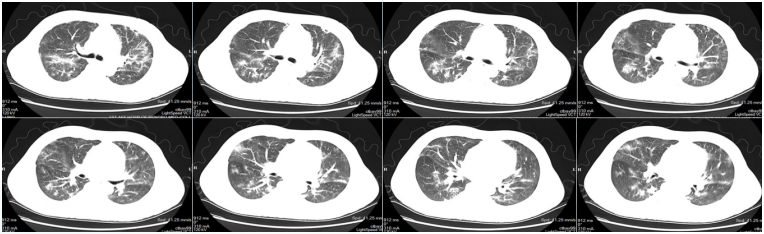

• 外院胸部CT(2024-07-11):两肺弥漫斑片状模糊影,双侧少量胸腔积液(图16)

16  患者外院胸部CT(2024-07-11)